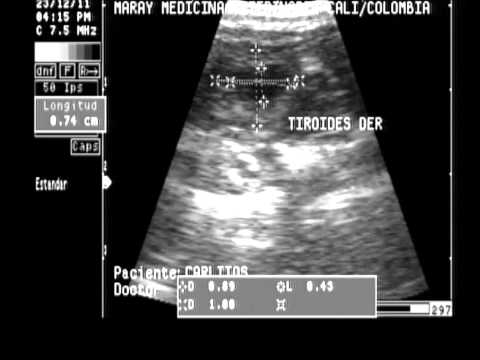

Bueno tengo hipertiroidismo y tengo un bulto enorme en el tiroides apreciable por fuera. Ya estoy operada de un lado por lo tanto ha crecido en el otro y ya estan empezando hacerme pruebas para ver si es conveniente operarme que sinceramente que me lo quiten ya porque hasta me molesta tener eso ahi. Estoy empezando apreciar mucho cansancio, me paso mucho tiempo durmiendo porque estoy cansada. Ayer mi niño se comportó como un campeón acompañandome cuando no tenía porque, bueno una puncion te mareas pero no tenía porqué, solo pedirselo yo y vino. Bueno pues os quería poner de youtube lo que me hicieron ayer, claramente yo no tengo el video de mi antigua operacion ni de mis antiguas punciones y mucho menos de las resonancias pero para que os hagais una idea. Ah hoy tambien he ido al psiquiatra y me ha bajado medicación por lo que se confirma que San Judas Tadeo está cumpliendo asi que ya os pondre para hacer la novena de San Judas Tadeo.